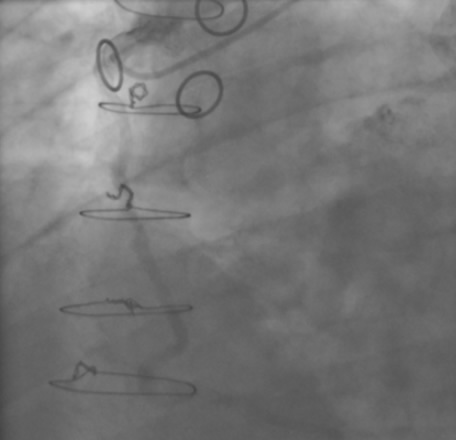

The most commonly used catheters for left heart catheterization and vein graft angiography can be seen in Figure 1 and Figure 4-13. Most of the vein grafts have horizontal take off and can be successfully engaged using a commonly used Judkins right number 4 (JR4) catheter. The JR4 catheter is the most commonly used catheter for the engagement of the right coronary ostium with horizontal take off. However, many vein grafts have unusual take off requiring different catheters. Many right coronary vein grafts have steep inferior take off making the ostial engagement with JR4 difficult or impossible (Figure 10). In such a scenario, a multipurpose catheter which has a shallow angulation is the best choice (Figure 11). The second major challenge in engaging vein graft ostia, particularly vein grafts supplying the left coronary arteries, is the shape of the aorta. A large aorta can make it very difficult for the JR4 catheter to reach the ostial vein grafts. In such a situation, Amplatz (AR) right and left (AL) catheters can be very helpful to reach the vein graft ostia. Amplatz catheters have a larger primary curve and have been used successfully in unusual superior take off of left coronary arteries or vein grafts and in large aorta. Amplatz catheters are available in different sizes (from smaller to larger curve: AR 1, AR2, AL2, AL2 and AL3). Occasionally, a very superior take off of a vein graft requires specially designed bypass graft catheters. Amplatz catheters are also extremely helpful in engaging native right coronary ostium with anterior take off.

PCI of the vein and arterial grafts have unique challenges. For any PCI, guide support is very important for successful balloon and stent delivery. In a tortuous vein graft with a steep angle, advancement of a stent can be very difficult and challenging. Therefore, it is important to choose the best available catheter before starting PCI. Similar to the right coronary angiography, a JR4 guide catheter is most commonly used in this setting. However, Amplatz guide catheters for left vein grafts and multipurpose catheters for right vein grafts are better choices in certain anatomy. In Figure 8 and Figure 10 two examples of poor guide support in two vein graft interventions can be seen. Initially, a JR4 guide was used for PCI of the vein graft supplying the left anterior descending artery (LAD) without any success. However, after changing the guide to an Amplatz left 2 guide catheter, we achieved excellent support without any difficulty in advancing two stents (Figure 9). In Figure 10, difficulty is illustrated in engaging the vein graft ostium supplying the right coronary artery with a JR4 catheter. This vein graft has a very steep inferior take off from the aorta. After changing the guide to a multipurpose catheter, we were able to deliver three stents successfully without any difficulties (Figure 11). Similar challenges exist in the treatment of the left IMA or right IMA. These arterial grafts can be extremely tortuous making stent delivery very difficult. It may be necessary to use short length stents for a better deliverability or stents with lowest profile. Usually, similar to the native coronary intervention, a 6 French guide is appropriate for the routine use.